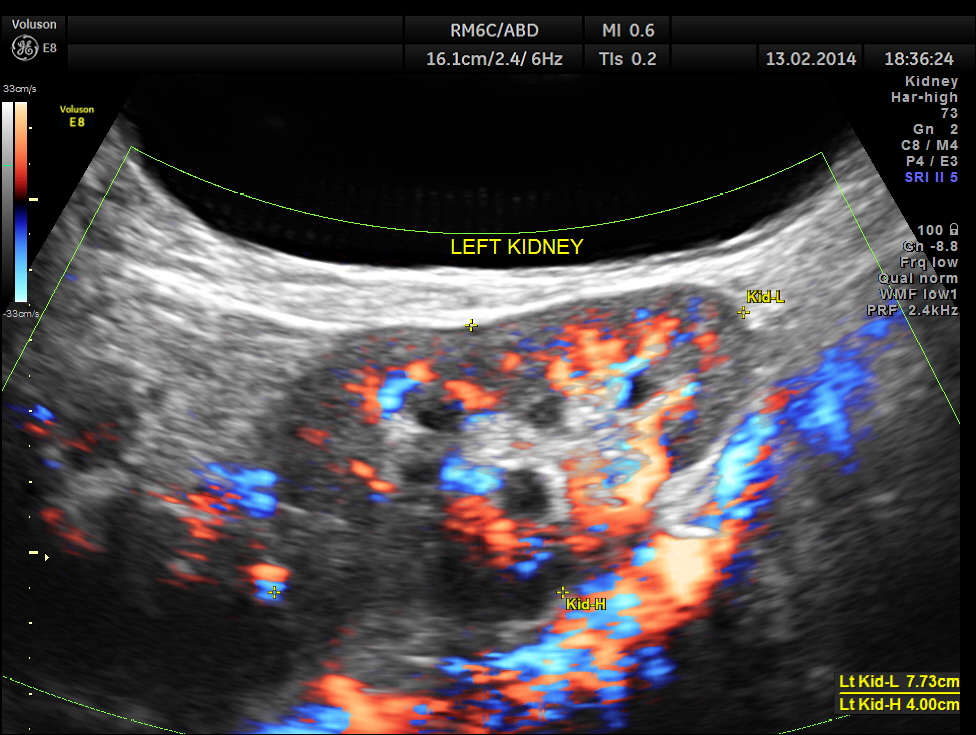

The following are the pictures of the kidney , which show the congenital horse shoe kidneys , placed ectopically in the pelvis. He had no urinary symptoms or low back ache at any time .

The right and left portions of the horse shoe are shown separately below

The power doppler pictures are given below.